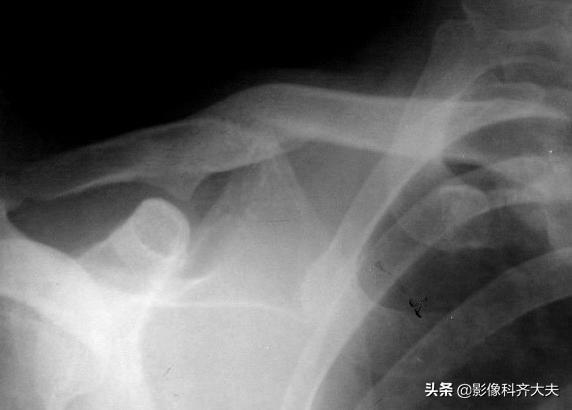

肱骨骨折

肱骨远端骨折后大量骨痂形成,骨小梁穿越骨折处